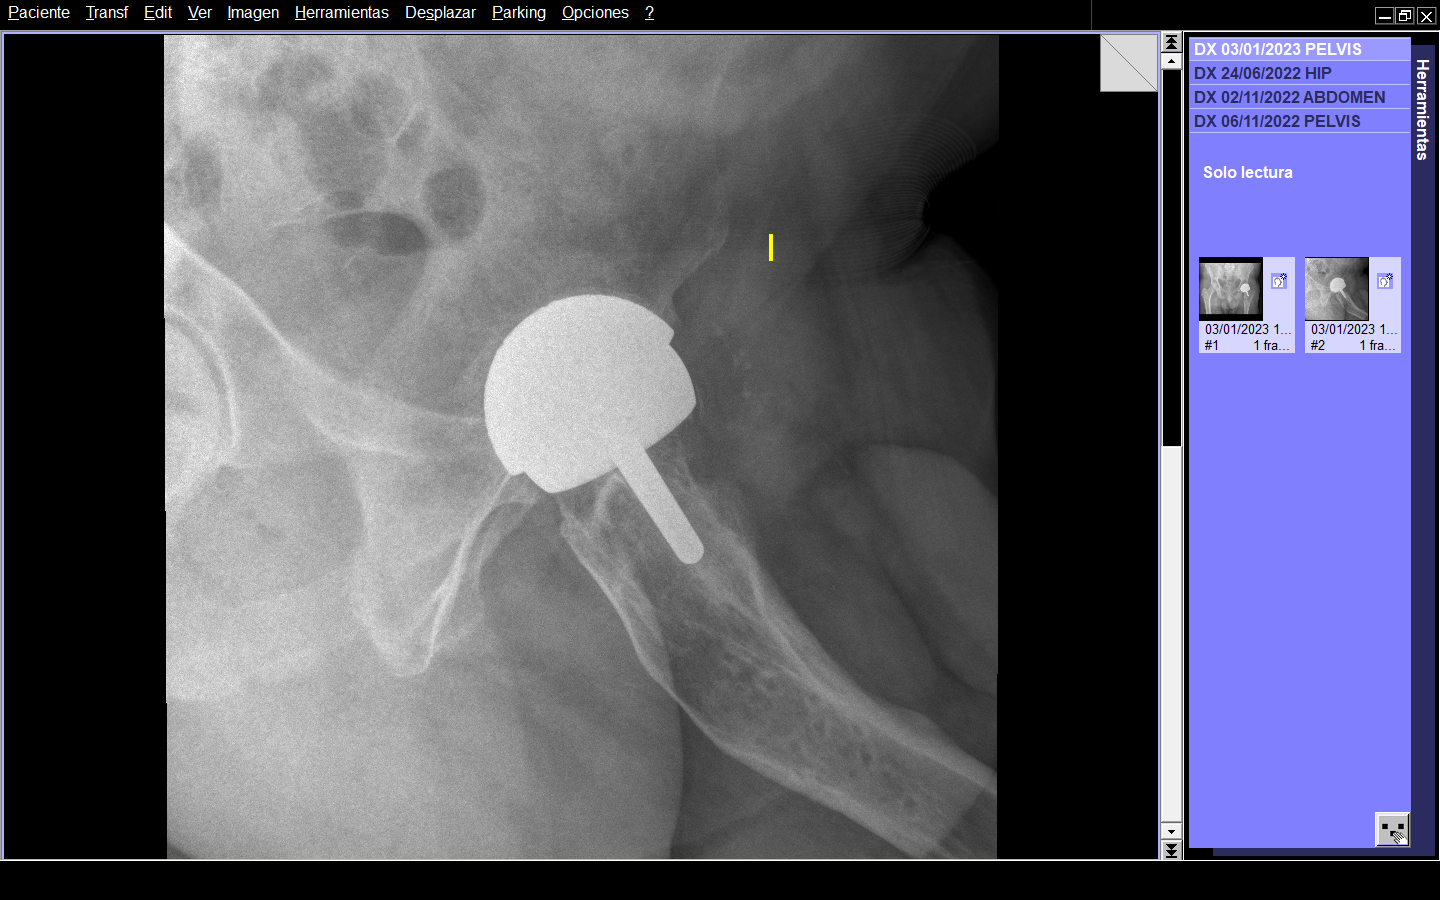

Hasta la fecha, el seguimiento a seis meses de la cirugía el paciente no presenta dolor y deambula sin muletas. A la movilización de la cadera izquierda, ésta presenta un rango de movilidad completo y con una funcionalidad total a la vida diaria. (Figura 5 y 6)

Figura 5. Radiografía al seguimiento a seis meses del paciente.

Figura 6. Radiografía axial al seguimiento de seis meses.